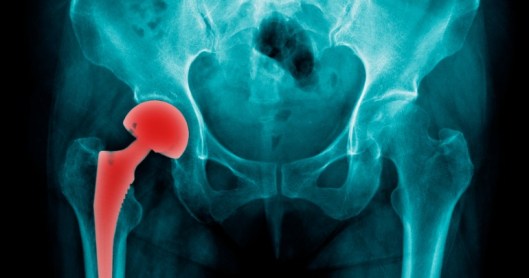

The metal hip implants are under the spotlight.

There are concerns thousands of people could be at risk of heart problems and dementia because of toxic material found in hip replacements.

Medical regulators are investigating the issue, which stems from cobalt and chromium used in metal-on-metal hip implants, reports News Corp.